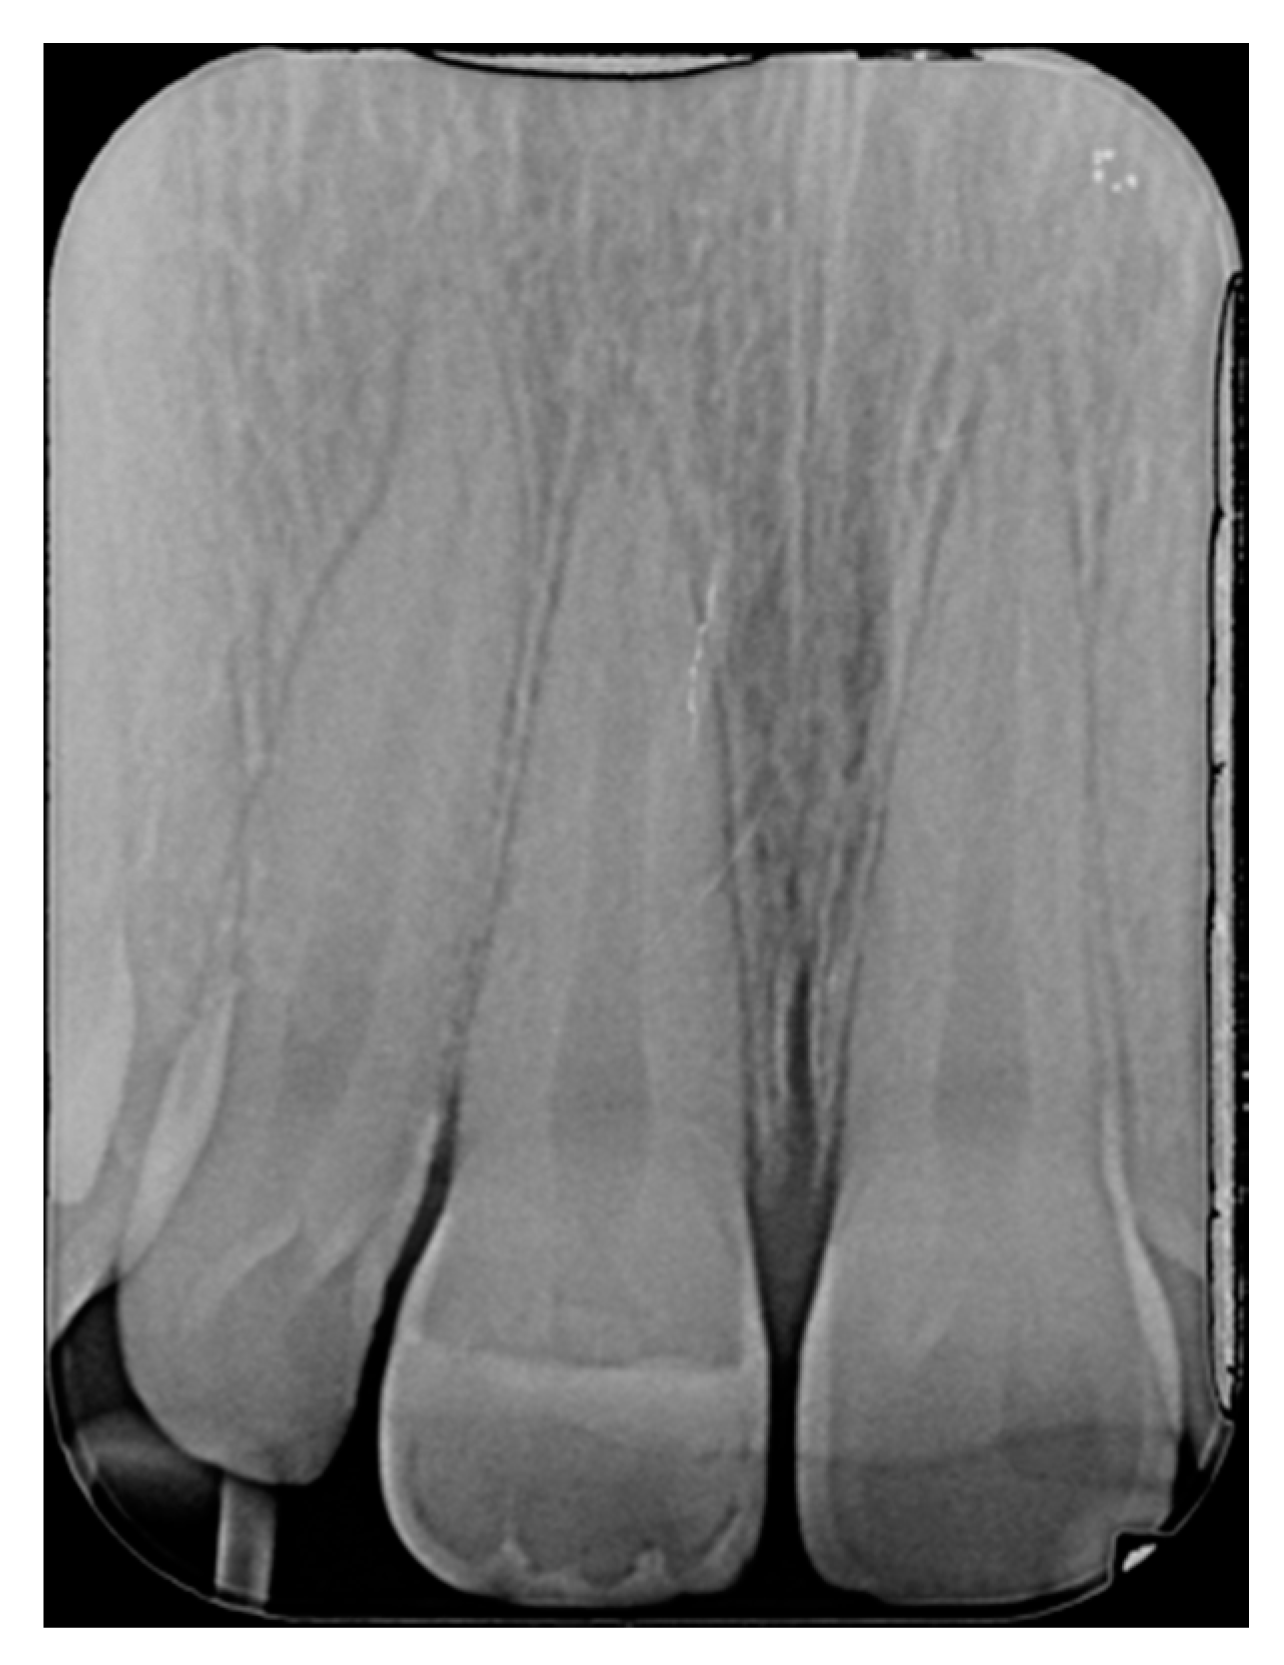

Finishing and polishing procedures were performed with a diamond bur (WL 268 014 Horico, Berlin, Germany), silicone points (Identoflex, Kerr, Bioggio, Switzerland) brushes (Jiffy Goat Air Brushes, Ultradent Products, South Jordan, UT, USA), and diamond pastes (Diamond Polish Mint, Ultradent Products, South Jordan, UT, USA) (Figure 13 and Figure 14). Satisfactory clinical and radiographic outcome was considered satisfactory at 3-months, 1-year, and 5-years post-operative (Figure 15, Figure 16, Figure 17, Figure 18 and Figure 19).

Figure 17.

One year post-operative x-ray. Reprinted from Restauri diretti nei settori anteriori, G. Paolone, S. Scolavino, © 2021, with permission from Quintessence Publishing Italy.

Figure 18.

Five years post-operative.

Figure 19.

Five years post-operative x-ray.